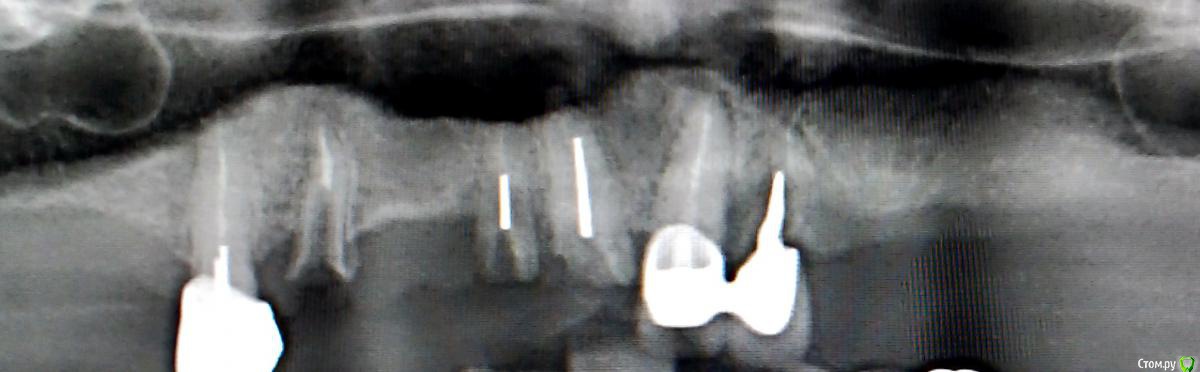

Здравствуйте! После того, как сняли мост с верхних 1-4 зубов, то рекомендовали удалить оставшиеся зубы и корни зубов и ставить съемный протез на верхнюю челюсть. Говорят, что оставшиеся корни не вынесут мост долгое время. Сами корни без сколов или воспалений.

Вопрос: возможно ли заличить корни и оставить их под съемный протез? По логике вещей, не должна ли кость с оставшимися корнями быть более укрепленной, чем после экстракции? Такое вообще делается?

Снимок прилагается.